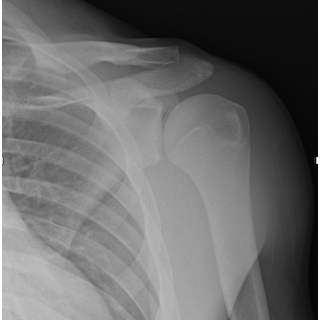

| Tackling Trauma: Recurrent Shoulder Injuries In A Football Athlete - Page #3 | |||